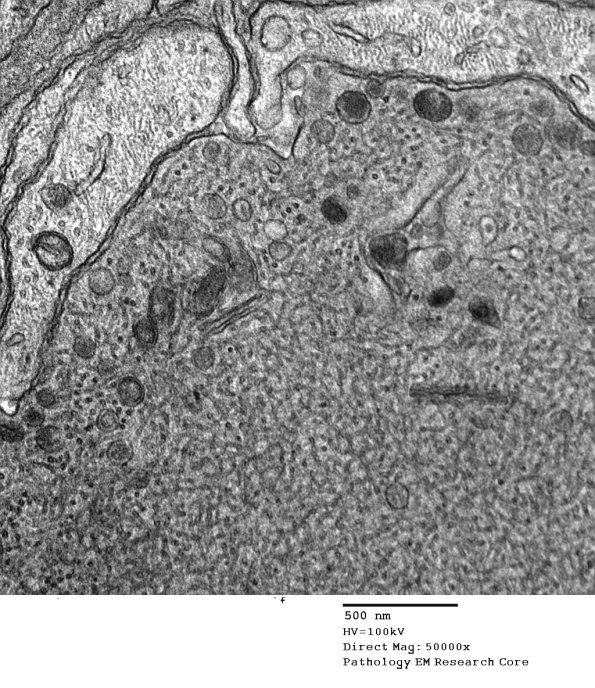

Shown is a band of Büngner with an axon swollen with tubulovesicular elements. (electron micrographs)